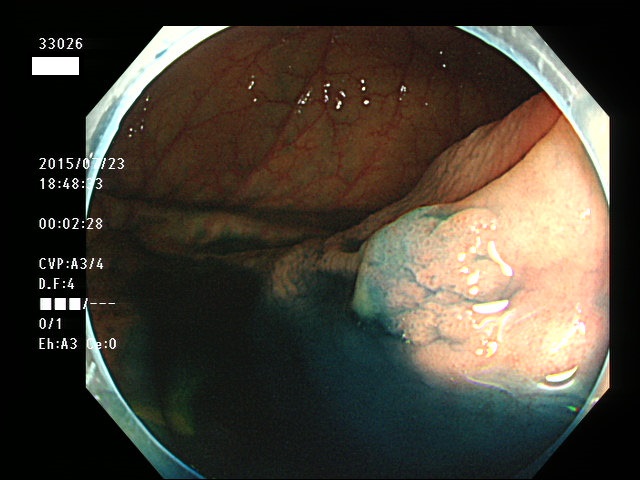

上記100名より抽出した平坦・陥凹型腺腫(=癌化の危険が高いが見落としやすい病変)の内視鏡写真

33003 33004 33005 33006 33007 33008 33009 33010 33011 33012 33013 33014 33015 13306 33018 33021 33024 33025 33026 33029 33030 33031 33032 33033 33036 33038 33039 33041 33042 33045 33046 33048 33051 33053 33054 33055 33057 33060 33063 33066 33068 33069 33071 33072 33074 33077 33078 33080 33086 33088 33089 33090 33091 33093 33095 33096 ・・・・・・の56名